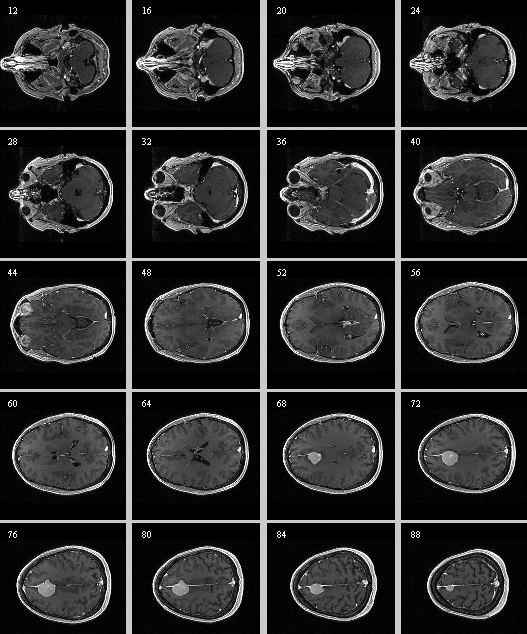

• Content preview: Have a quick look before downloading: Does your data look like this? Media:RegUC2_lightbox.png